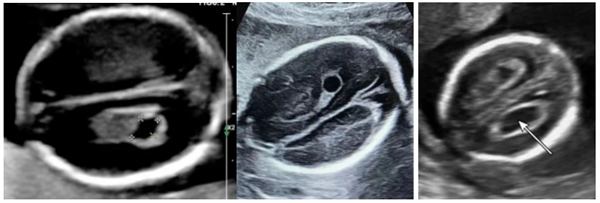

信号三:脉络丛囊肿——大脑里的“临时工地”

B超单提示:“脉络丛囊肿”

它是什么?大脑中产生脑脊液的“泉水源头”(脉络丛),在发育过程中形成的临时性“小水囊”。

医生解密:

1.发育的“小插曲”:是大脑发育过程中的常见伴随现象。

2.超高吸收率:超过90%的囊肿在孕26-28周后会被大脑自然吸收。

3.它完全不影响宝宝未来的智商和大脑功能。

4.孤立存在无意义:单纯不合并其他异常的囊肿,临床意义极小。